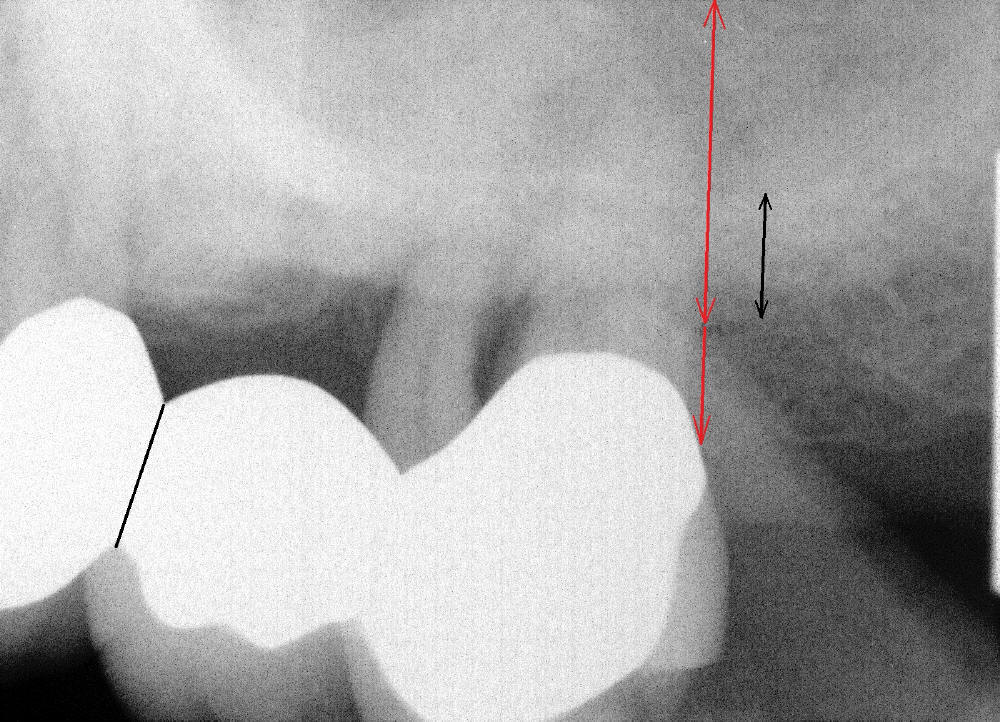

病人要求先处理左上桥(图二,五),我们准备在五六号牙之间切断桥(图六:黑线),拔除七号牙,立刻植牙。那里骨头高度多少?是黑线,还是红线?一两天我们就会给您答复。估计在那里可以植入七或者八乘十一或者十四毫米植牙。

如果时间允许,我们可能同时在左上六号牙处植牙,骨头高度好像不乐观(图五,六),积极人在图二找骨头,估计可以植入六乘十一或者十四毫米植牙。